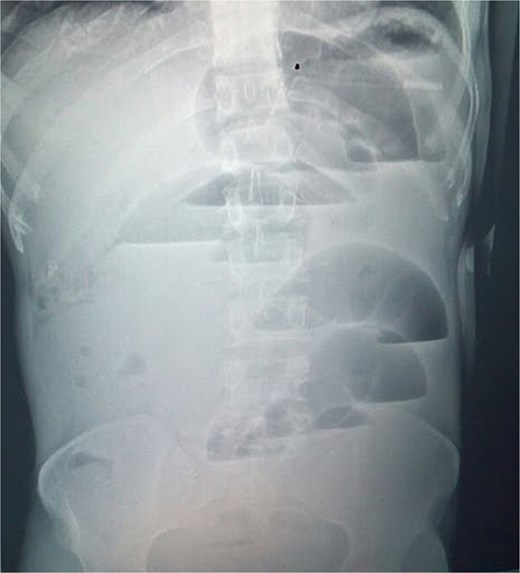

Inflamed appendix forming a constricting ring (arrow) around a loop of viable distal ileum (arrow head).

After consent, prophylactic ceftriaxone 1 g IV and metronidazole 500 mg IV were administered 30 minutes preincision and continued for 24 hours, per clean-contaminated prophylaxis. Midline laparotomy revealed minimal reactive fluid and an inflamed appendix forming a tight ring around ~15 cm of distal ileum, <10 cm proximal to the ileocecal valve (Fig. 2). The appendiceal tip adhered to the distal ileal mesentery, causing luminal obstruction without a complete tourniquet. There was no mesenteric twist or pedicle occlusion; mesenteric arterial pulsations were palpable with brisk capillary refill and active peristalsis. The proximal bowel was markedly distended yet viable (Fig. 3).